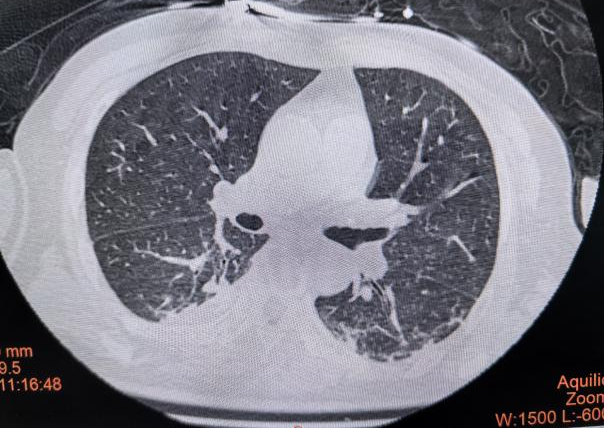

经过积极治疗,患者肺部感染逐步得到控制,肺实变明显吸收。复查EIT图像可见,双肺通气分布较前显著改善,通气均匀性恢复,局部塌陷区域成功复张。这一动态、可视化的改善过程,为临床疗效评价提供了客观、有力的证据,充分展现了EIT技术在指导重症肺炎患者呼吸机精细化管理及疗效评价方面的重要临床价值。